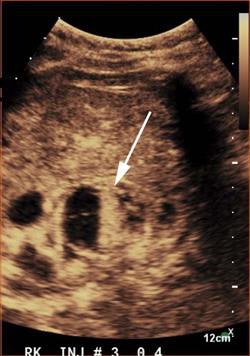

After first receiving conventional grayscale ultrasound to localize the renal lesion and determine the best plane for the contrast study, the CEUS exams were performed using a low mechanical index on either an iU22 (Philips Healthcare) or Epiq 7 (Philips) ultrasound scanner equipped with a C5-2 or C9-2 transducer. Once they had completed a safety questionnaire to assess for any potential contraindication to receiving microbubble contrast agents, the patients received intravenous bolus injections of the Definity (Lantheus Medical Imaging) or SonoVue (Bracco Diagnostics) ultrasound contrast agents. Most patients received one to three doses of contrast material, depending on if there were multiple lesions or if additional imaging was necessary, according to the researchers.